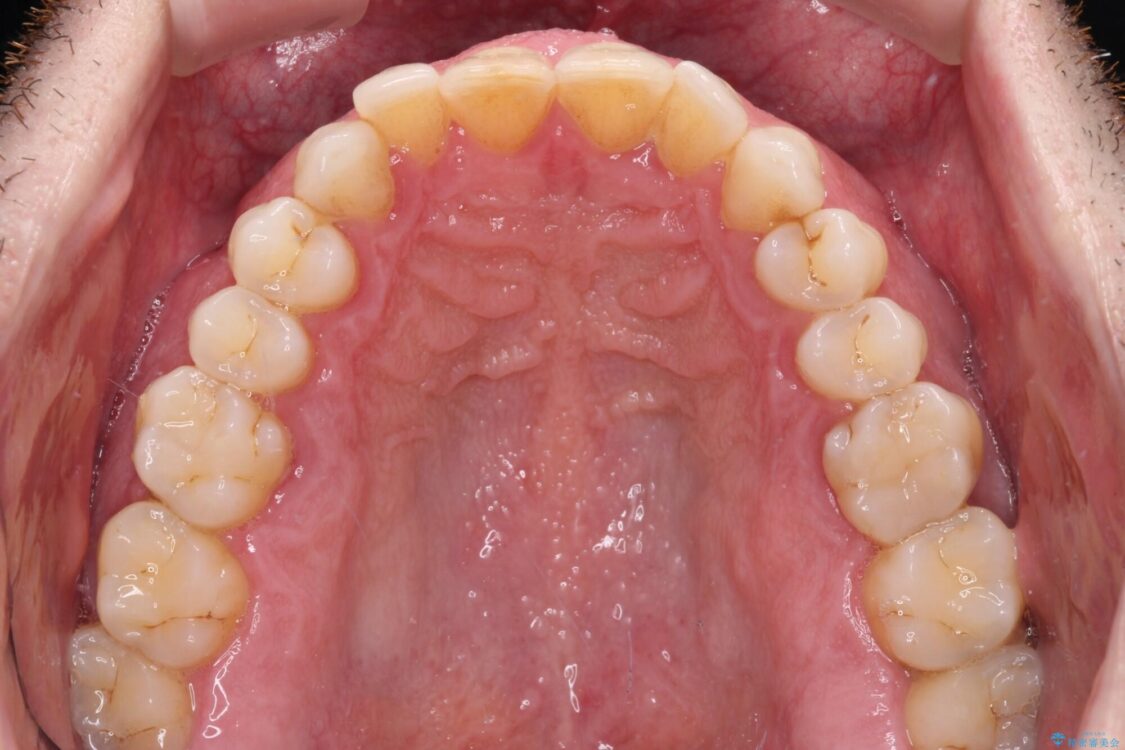

治療前

• 前歯でものを噛みきりたい 目立たない装置でのワイヤー矯正 治療前画像